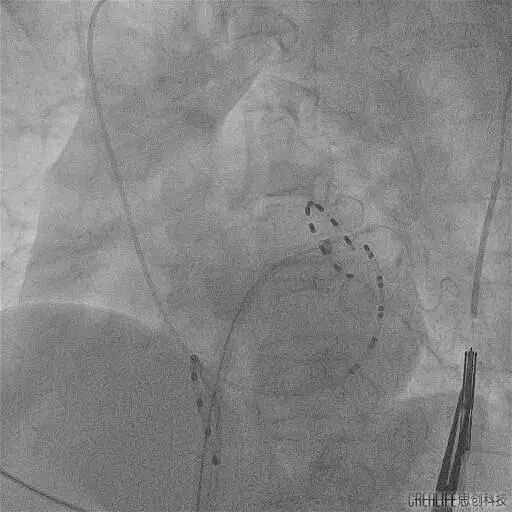

今年60岁的崔伯伯(化名)和59岁的张阿姨(化名)因房颤发作频繁,极大的影响日常生活,甚至呈焦虑状态,遂就诊武汉亚洲心脏病医院;在完善心脏彩超、食道超声及左房CT等一系列检查后,张劲林主任和韩宏伟主任经过充分的评估和与患者及家属的知情确认后,选择脉冲电场消融术为其治疗,该项技术以其高安全性、高效性和微创性,为房颤患者带来了更为优质的治疗选择。术中使用脉冲电场消融导管分别在四根肺静脉进行消融,每根肺静脉口内定位4个位置,前庭定位6-8个位置,逐次放电(电压1500V) 。每根肺静脉首次放电,肺静脉电位振幅即可明显下降至消失,四根肺静脉均完成肺静脉电隔离。

PS导管通过外鞘送入左心房,在二维引导下到达目标肺静脉,在导丝指引下调整导管成环进入肺静脉,使环形电极贴靠肺静脉口/前庭。

观察电极形变并明确电位,确认贴靠良好后依次对每个每支静脉进行口部4次+前庭6-8次的脉冲消融,对上腔静脉补充4次消融,完成四根肺静脉(PVI)和上腔静脉的环形隔离。

PS导管行RSPV消融